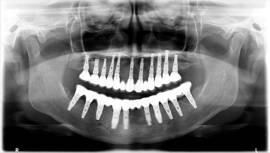

בלסת העליונה ביצענו עקירות כל השיניים בישיבה אחת עם הרמות סינוס משני הצדדים והתקנת 11 שתלים. בפגישה נוספת עבור הלסת התחתונה נעקרו גם כן כל השיניים עם ביצוע מיידי של 10 שתלים.

מייד בתום ההשתלות בכל לסת בוצעה העמסה מיידית עם גשרי אקריל זמניים שהוכנו מראש וסיפקו מענה תפקודי ואסטטי מצויין לתקופת ההמתנה.

בישיבה אחת לכל לסת בוצעו כל העקירות ,כל ההשתלות והתקנת גשר האקריל על מנת לאפשר למתרפאה לצאת עם שיניים בו ביום.

לאחר 6 חודשים וקליטת השתלים באופן מלא, קיבלה המתרפאה גשרי חרסינה קבועים ברמת דיוק ואסטטיקה מושלמים.